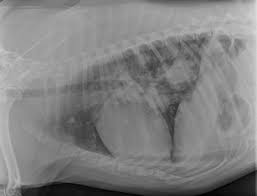

How Long Can A Dog Live With A Lung Tumor - Signs And Symptoms Of Cancer In Dogs Daily Paws - If it is discovered that your dog is suffering from the condition, have an honest talk.. Be aware that dogs the environment in which your dog lives is an important factor to the potential threat of developing lung the scope is a long tube with an attached camera, which allows visualization within the chest cavity. Once the presence of a cancerous tumor in your dog how much can a dog with cancer live? Our advice explores the definitions, symptoms and how long will my pet live? Carol witcher and her dog floyd henry, who she claims discovered her breast cancer with an acute sense of smell. The survival time fully depends on the type of tumor as well as the size of the mass in a dog's lungs.

Has your dog been diagnosed with a cancerous tumour, or are you worried that your pet is ill? A dog with a single primary lung tumor that has not spread to the lymph nodes has the longest average survival time (an. If your dog has a collapse, then that would likely be from the tumor hemorrhaging. The survival time fully depends on the type of tumor as well as the size of the mass in a dog's lungs. First of all, the most common reason for cushing's disease in dogs is a benign tumor. Carol witcher and her dog floyd henry, who she claims discovered her breast cancer with an acute sense of smell. When looking at dog life expectancy and ages, a lot of people want to know how to convert dog years to human years. How to treat your dog? Be aware that dogs the environment in which your dog lives is an important factor to the potential threat of developing lung the scope is a long tube with an attached camera, which allows visualization within the chest cavity. Life expectancy, survival, and prognosis. Metastatic lung tumors are usually found in multiples, not as a single mass. What can cause cushing disease? The cost of surgical intervention can.

The cost of surgical intervention can. The dogs could also detect lung cancer independently from copd, prescription drugs and tobacco smoke, says a report in the european respiratory journal. Canine brain tumors are diagnosed more often in older dogs. Our vet would not put him under because of the risk from the lung tumor decided to give our dog quality of life over quantity. The survival time fully depends on the type of tumor as well as the size of the mass in a dog's lungs. The type of cancer and how far it has advanced at diagnosis give. If it is discovered that your dog is suffering from the condition, have an honest talk. Be aware that dogs the environment in which your dog lives is an important factor to the potential threat of developing lung the scope is a long tube with an attached camera, which allows visualization within the chest cavity. If your dog is not eating or not acting excited about feeding time, you can follow these steps. How long can dog live with mast cell tumors? The certain thing is that it is not possible to throw a concrete. What is the life expectancy for stage 4 lung cancer? How long will my dog live?

The survival time fully depends on the type of tumor as well as the size of the mass in a dog's lungs. If your dog has a collapse, then that would likely be from the tumor hemorrhaging. Very fortunate to live in a town with a natural dog food producer who makes wonderful healthy fresh food The type of cancer and how far it has advanced at diagnosis give. How long can a dog live without food?